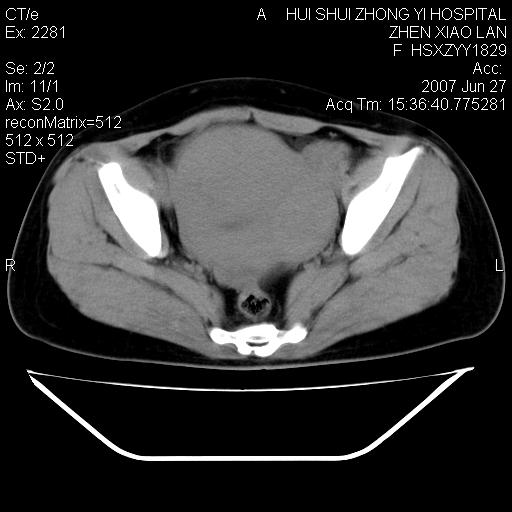

以下是引用还珠格格在2007-6-28 15:15:00的发言:[br]子宫明显增大,偏向盆腔右侧,密度均匀,和子宫同密度, 考虑 子宫肌瘤可能性大 建议增强 除外子宫平滑肌肉瘤。

以下是引用dyqct在2007-6-28 15:41:00的发言:[br]考虑多发子宫肌瘤可能性大,建议进一步增强检查。